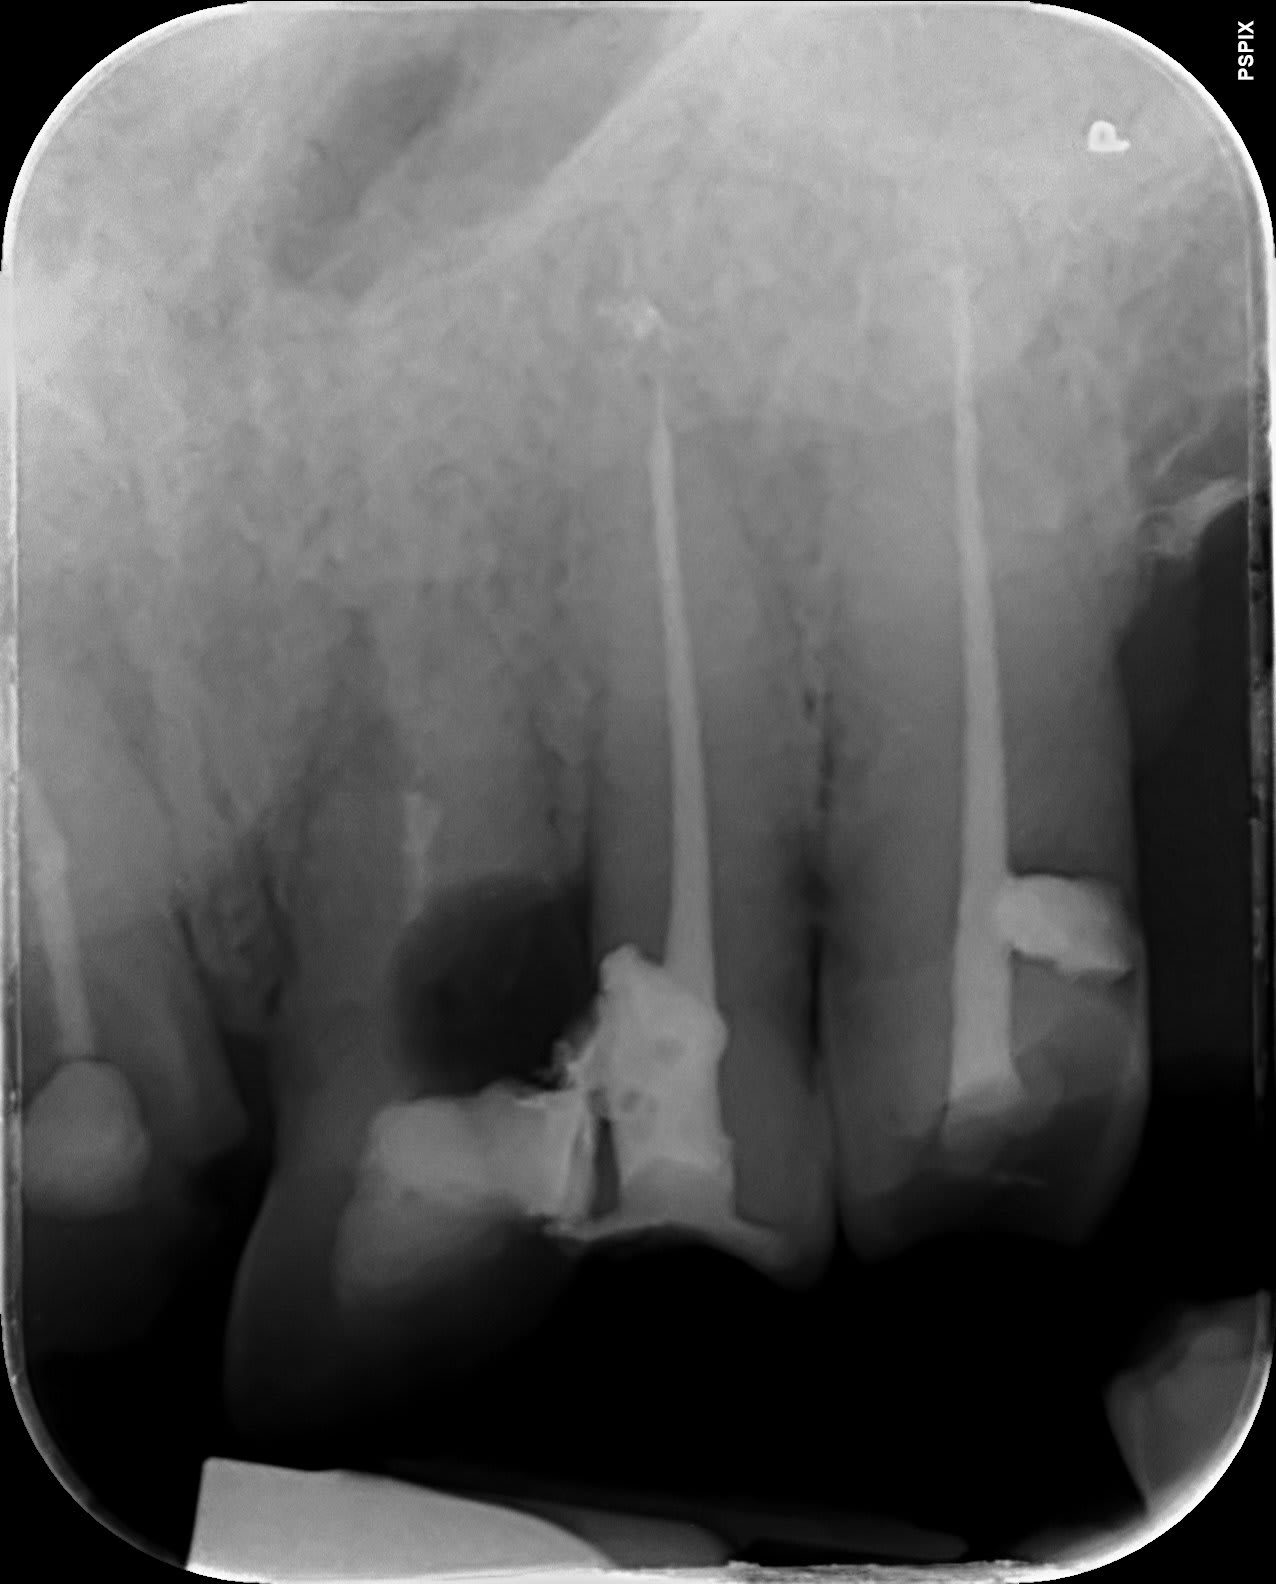

une autre radio qui explique un peu le dépassement, (enfin ça m'arrange de le penser) condensation trop forte pour avoir aussi les canaux accessoire.

Du tout simple gutta foulée plus ciment (septodon je crois a vérifier)